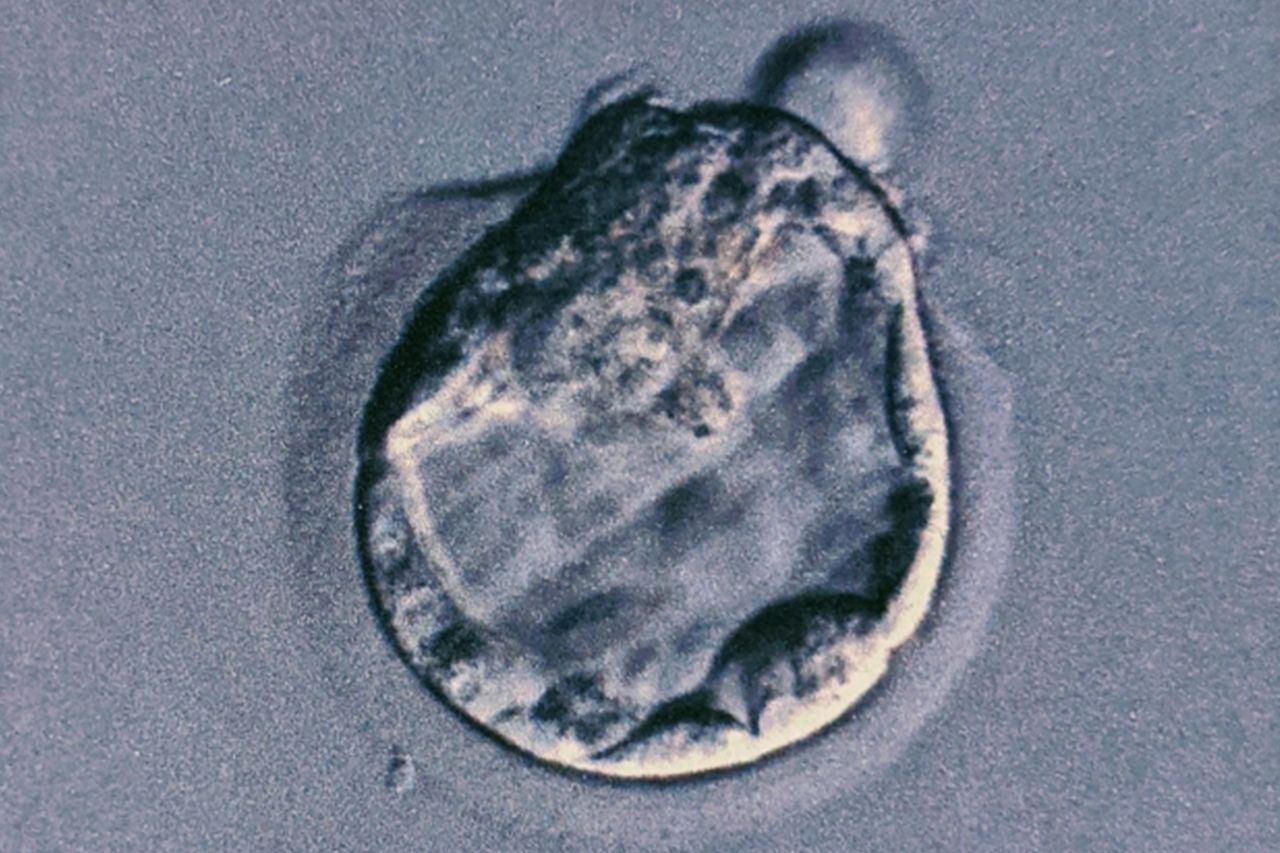

受精卵

[写真 8/8枚目] 受精卵